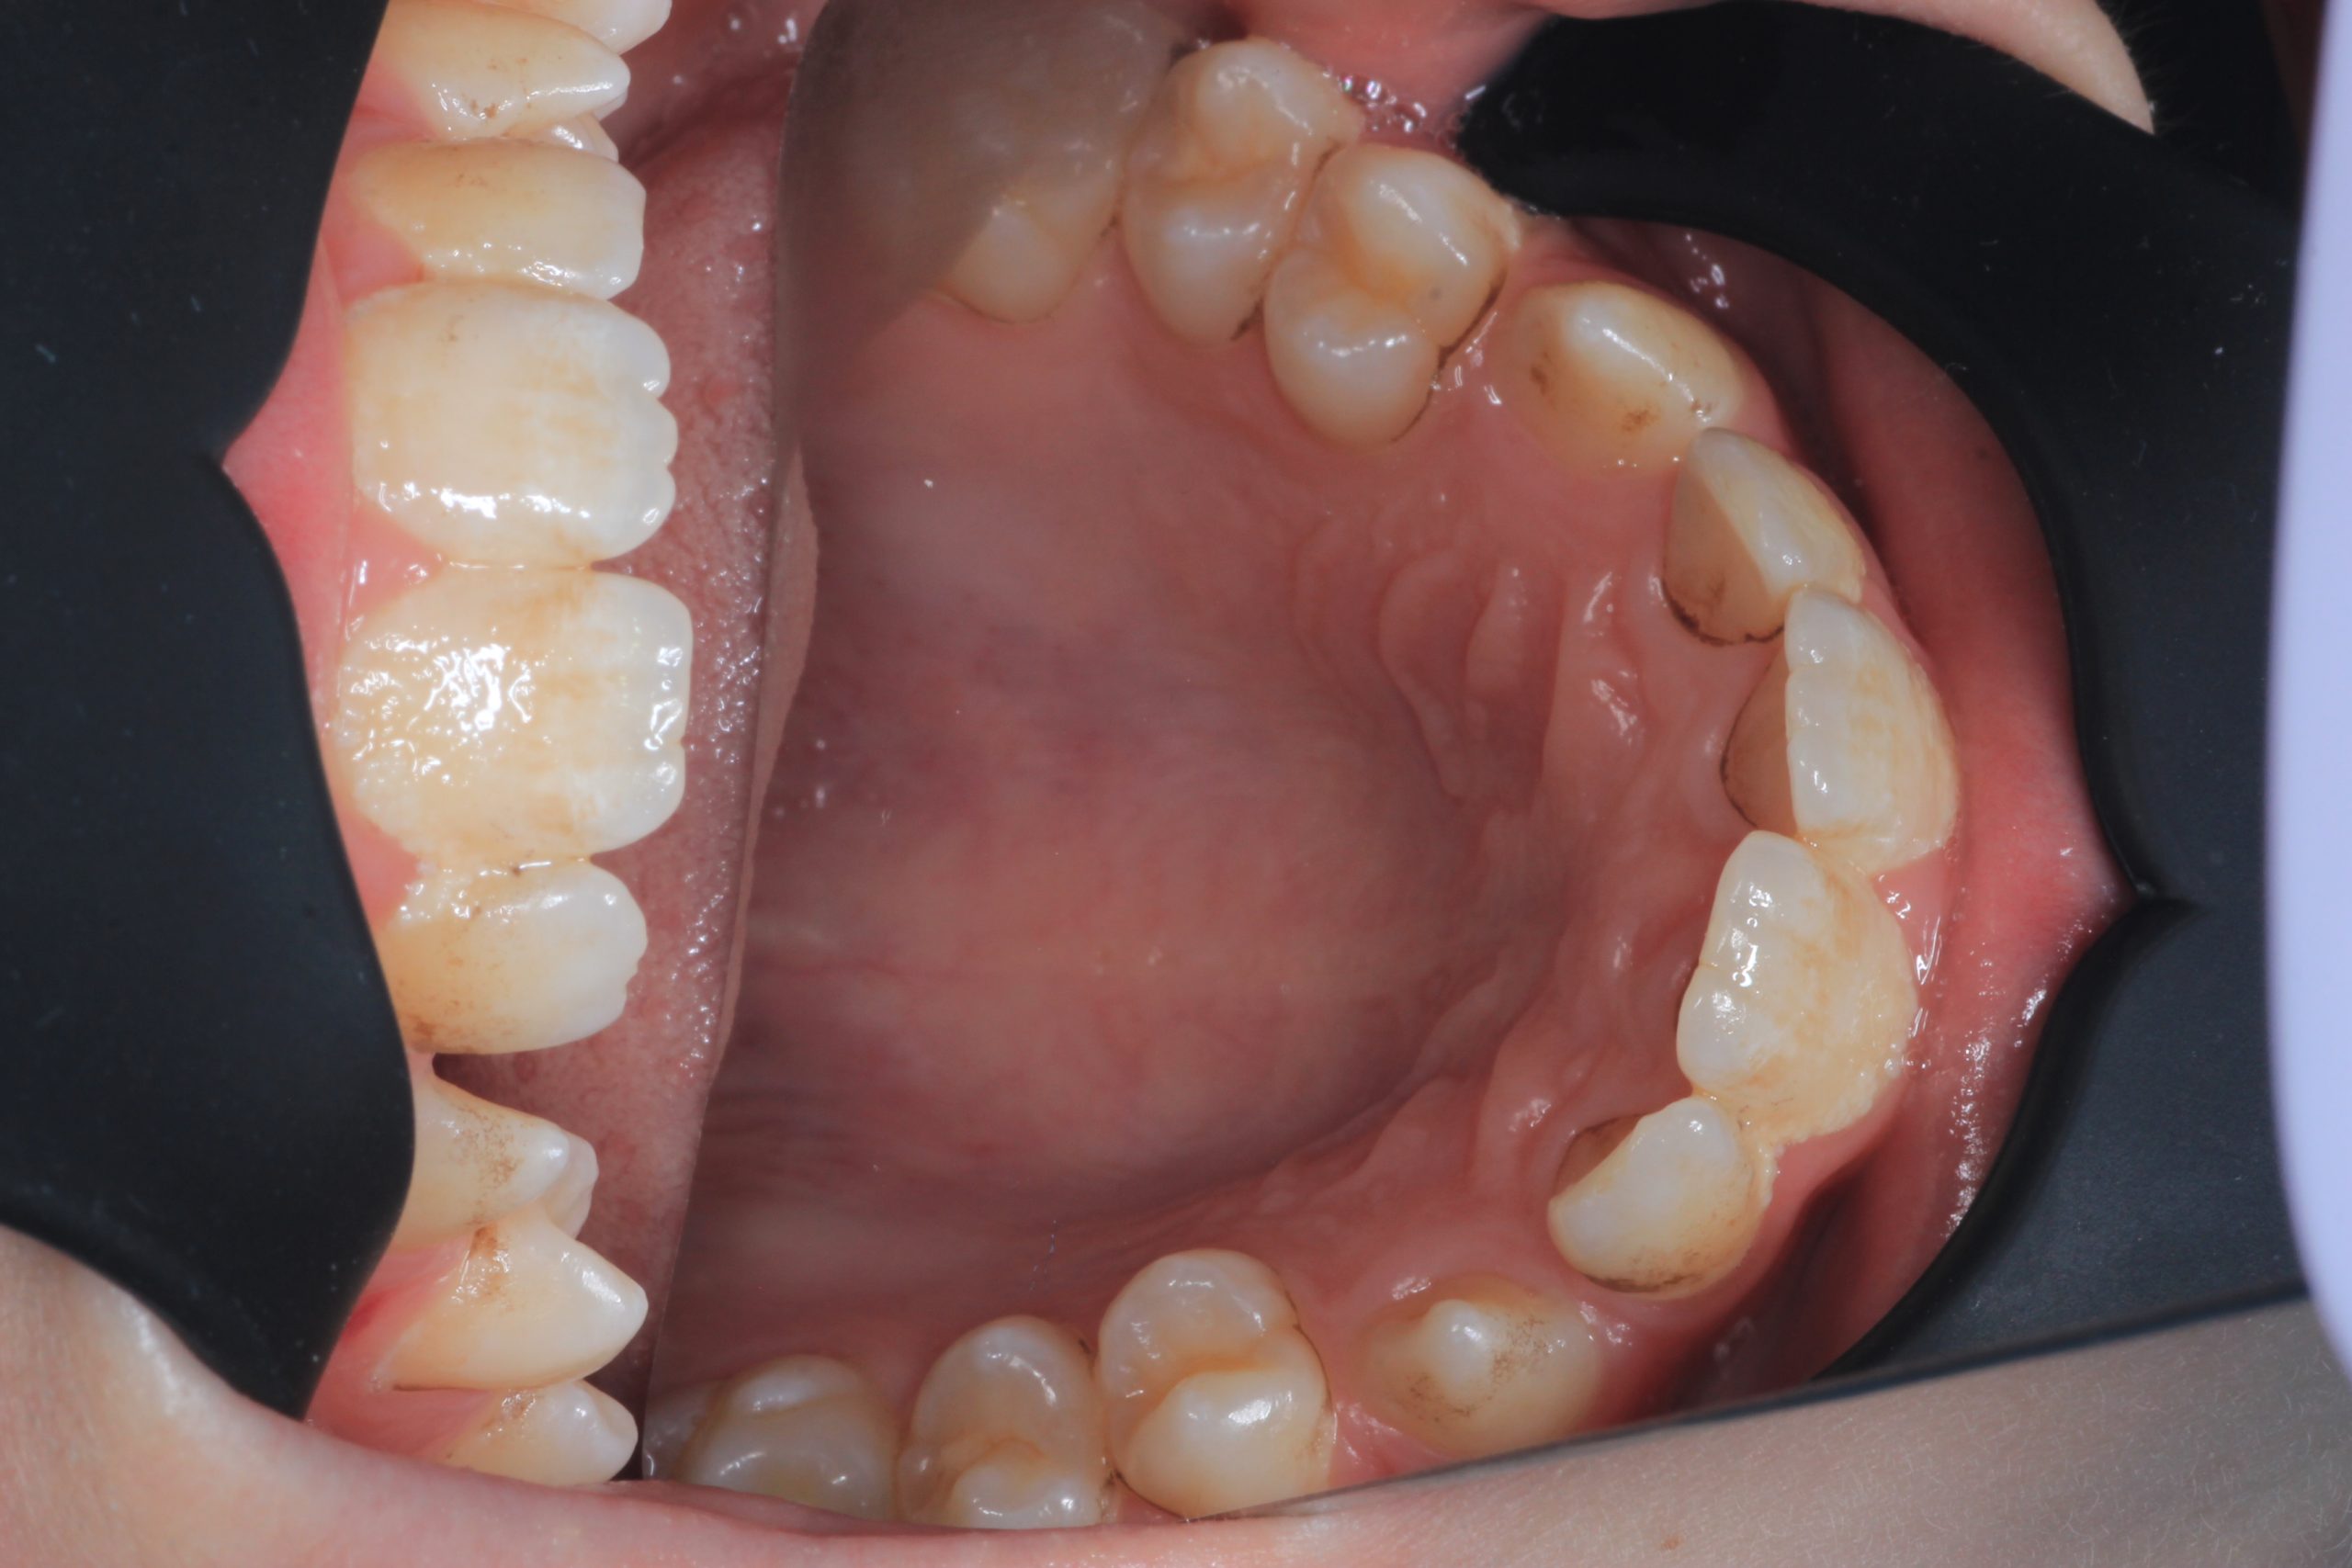

- Detailed Examination

We examine the condition of teeth, gums, and bite. - Plaque Disclosure with Special Indicators